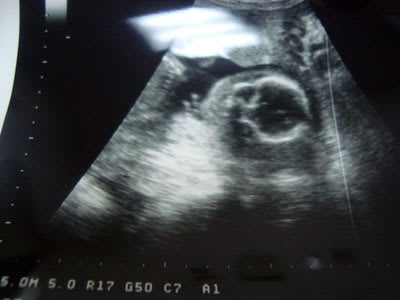

我が子の顔です♪頭5cmですって(笑)かわいい~♪

只今、21週と1日。

なんか、ピ~スしてるみたいだよ!頭蓋骨の下の手♪